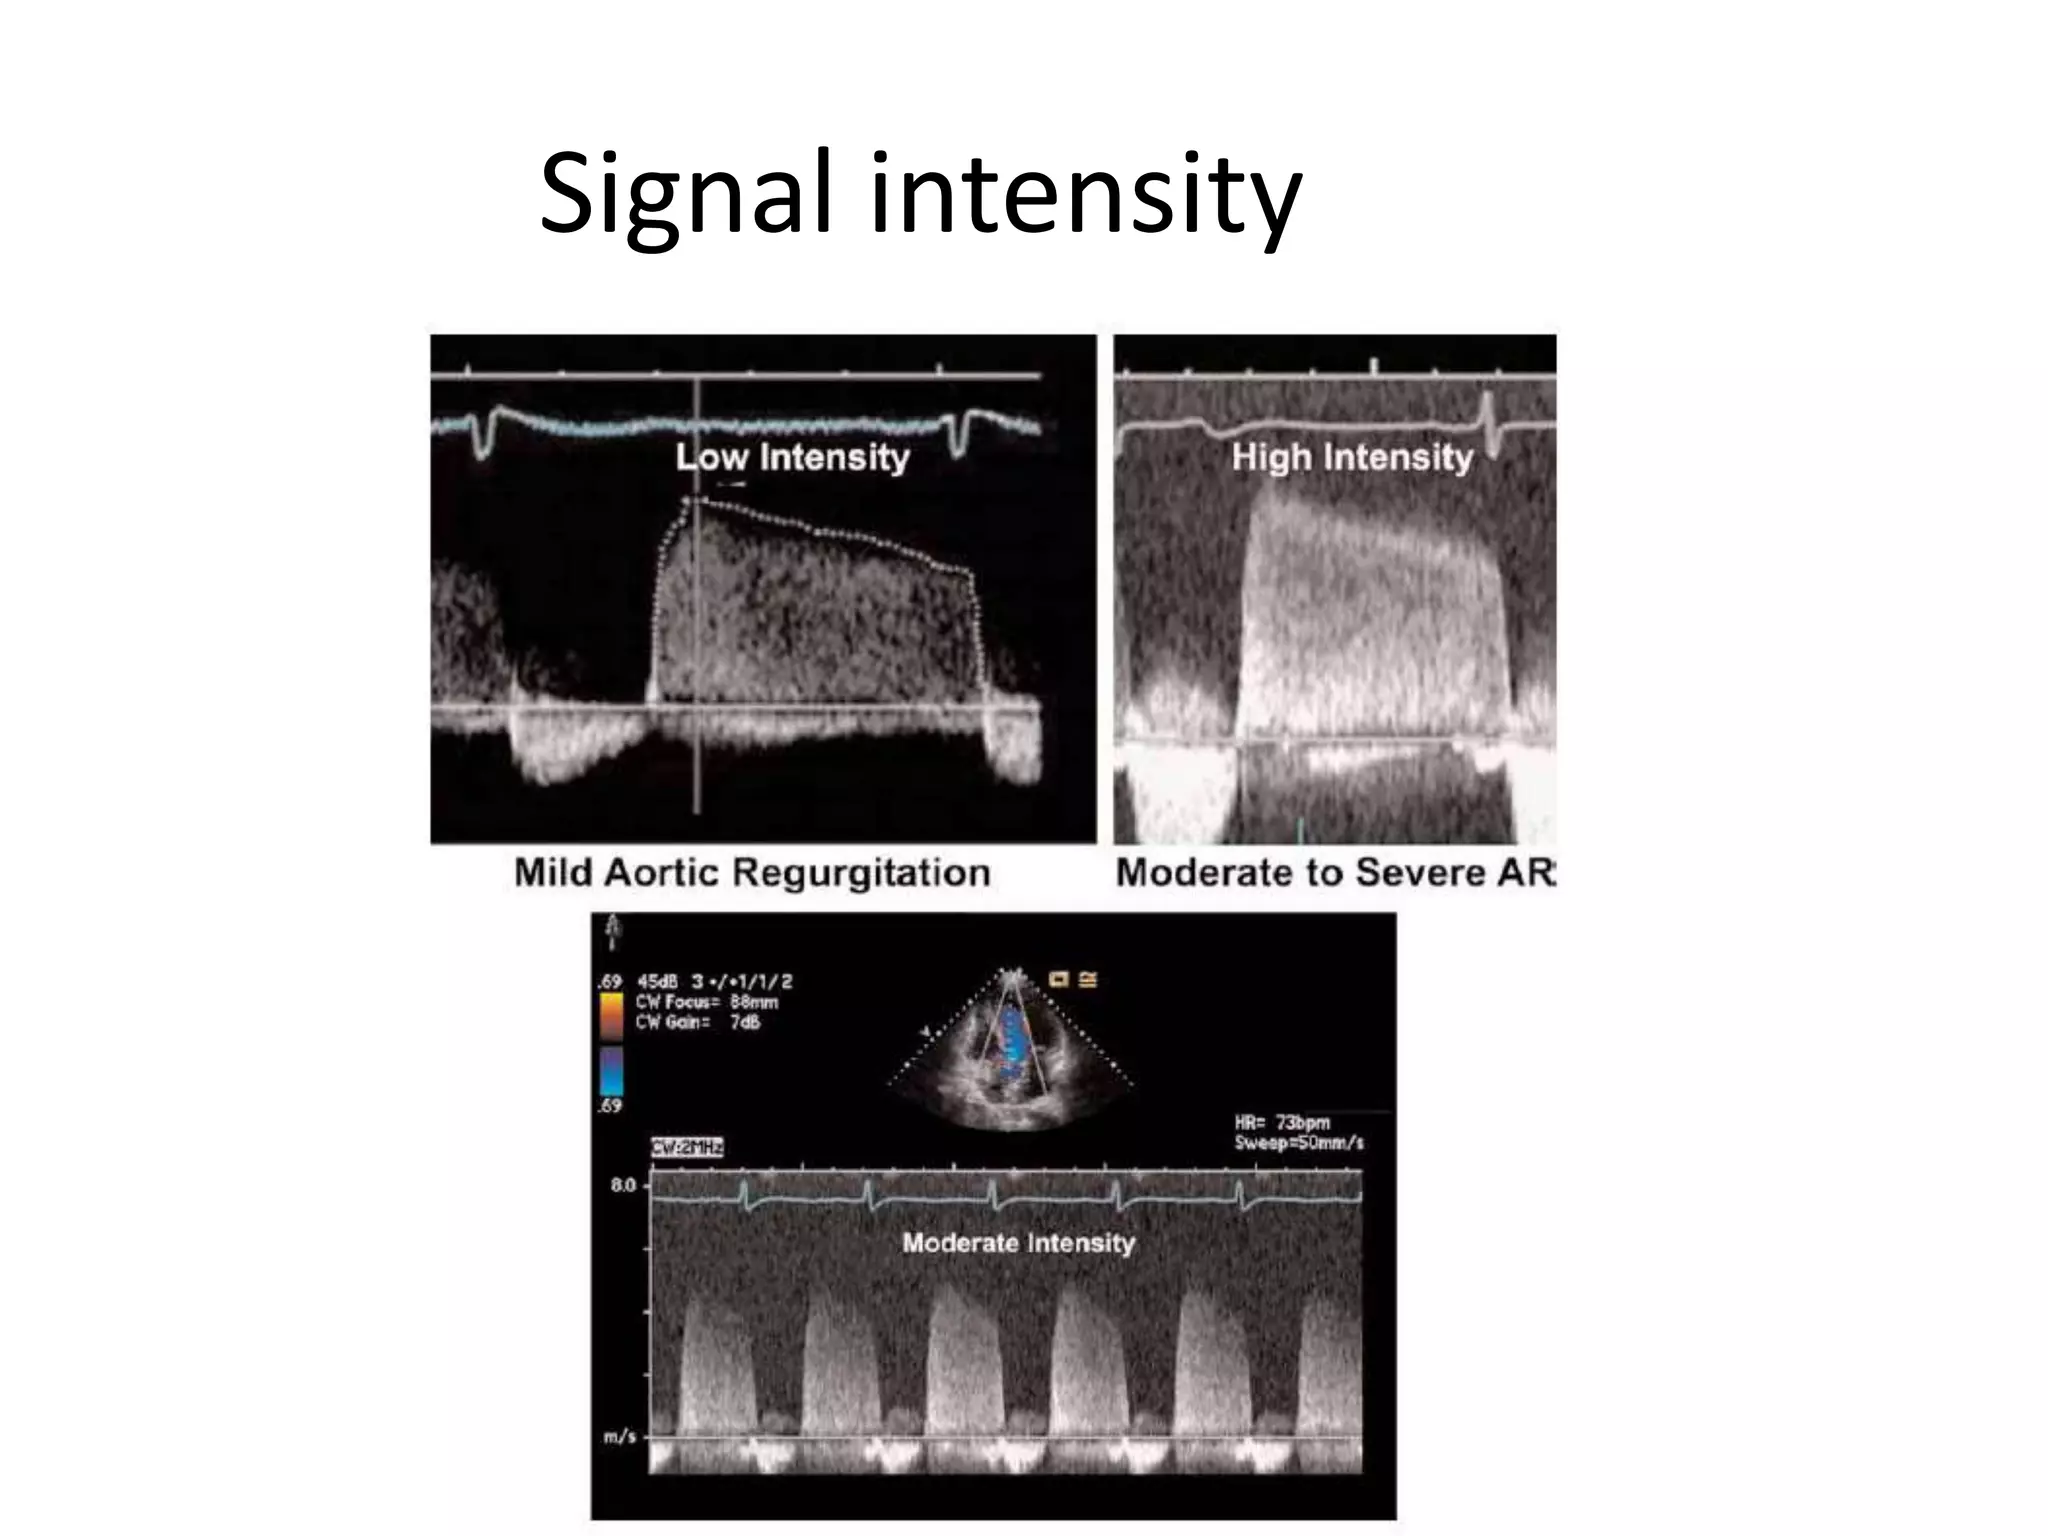

Extent of jet

Signal intensity